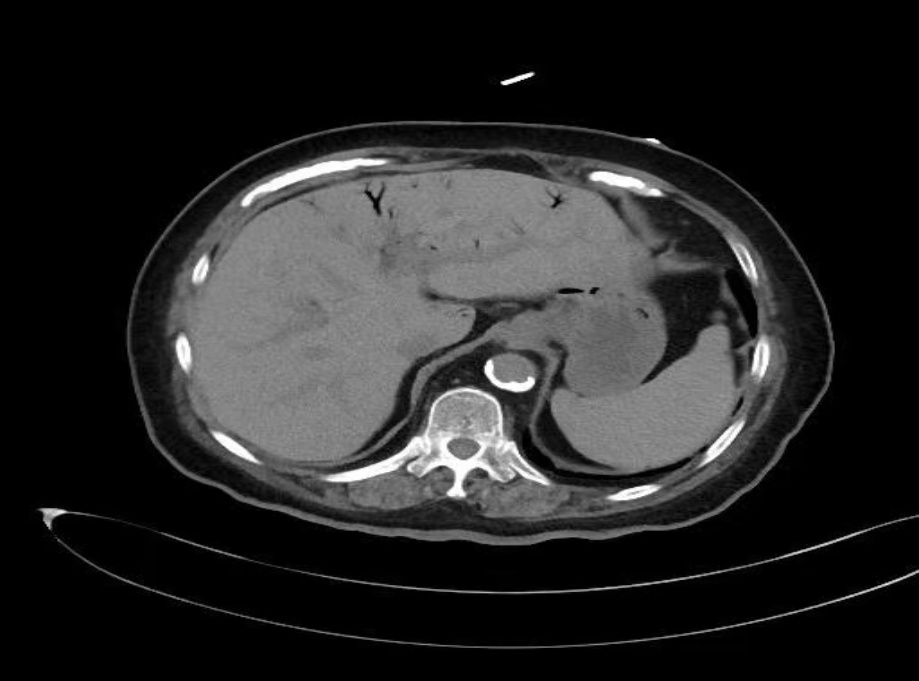

患者女性,72岁,诊断为2型糖尿病伴慢性肾功能不全,长期接受门诊血液透析治疗。本次透析2小时后突发持续性腹痛,伴呕吐3次,口服止痛药无效,遂于次日赴甘肃省人民医院普外科就诊。既往有高血压、糖尿病(30年)、冠状动脉粥样硬化性心脏病(冠脉支架植入术后1年)等病史,长期口服抗血小板药物。慢性肾衰竭10年,维持性血液透析10年,方案为每周3次,每次4小时。入院查体:血压126/74 mmHg,体温36.5℃,下腹部存在压痛、反跳痛及轻度肌紧张。腹部CT提示广泛肝门静脉积气,累及脾静脉、肠系膜上静脉、门静脉主干及肝内分支(见图1(a))。实验室检查白细胞计数升高(16.2 × 109/L),中性粒细胞百分比显著增高(93.80%),C-反应蛋白(76.50 mg/L),动脉血乳酸轻度升高(2.30 mmol/L)。因患者高龄,急性腹痛,既往2型糖尿病病史、长期血液透析,目前CT检查提示肝门静脉积气,经血管外科、重症医学科、心内科、内分泌科等多学科会诊,血流动力学稳定,且乳酸水平未显著升高,考虑肠坏死可能性较低,与患者家属充分沟通后,决定实施保守治疗。方案包括静脉输注头孢哌酮舒巴坦钠抗感染、禁食、补液、营养支持及低流量吸氧,治疗过程中密切监测病情变化。住院第6天复查腹部CT,显示肝内积气完全吸收(见图1(b))。患者出院后随访半年,一般情况稳定,未出现新发并发症。

(a) (b)

Figure 1. Plain abdominal CT scan images of the patient

1. 患者腹部CT平扫图像

图1(a):肝内多发积气影,沿门静脉及其分支走行,肝实质未见明显异常密度影;图1(b):治疗后肝内积气已消失,肝实质未见明显异常密度影。